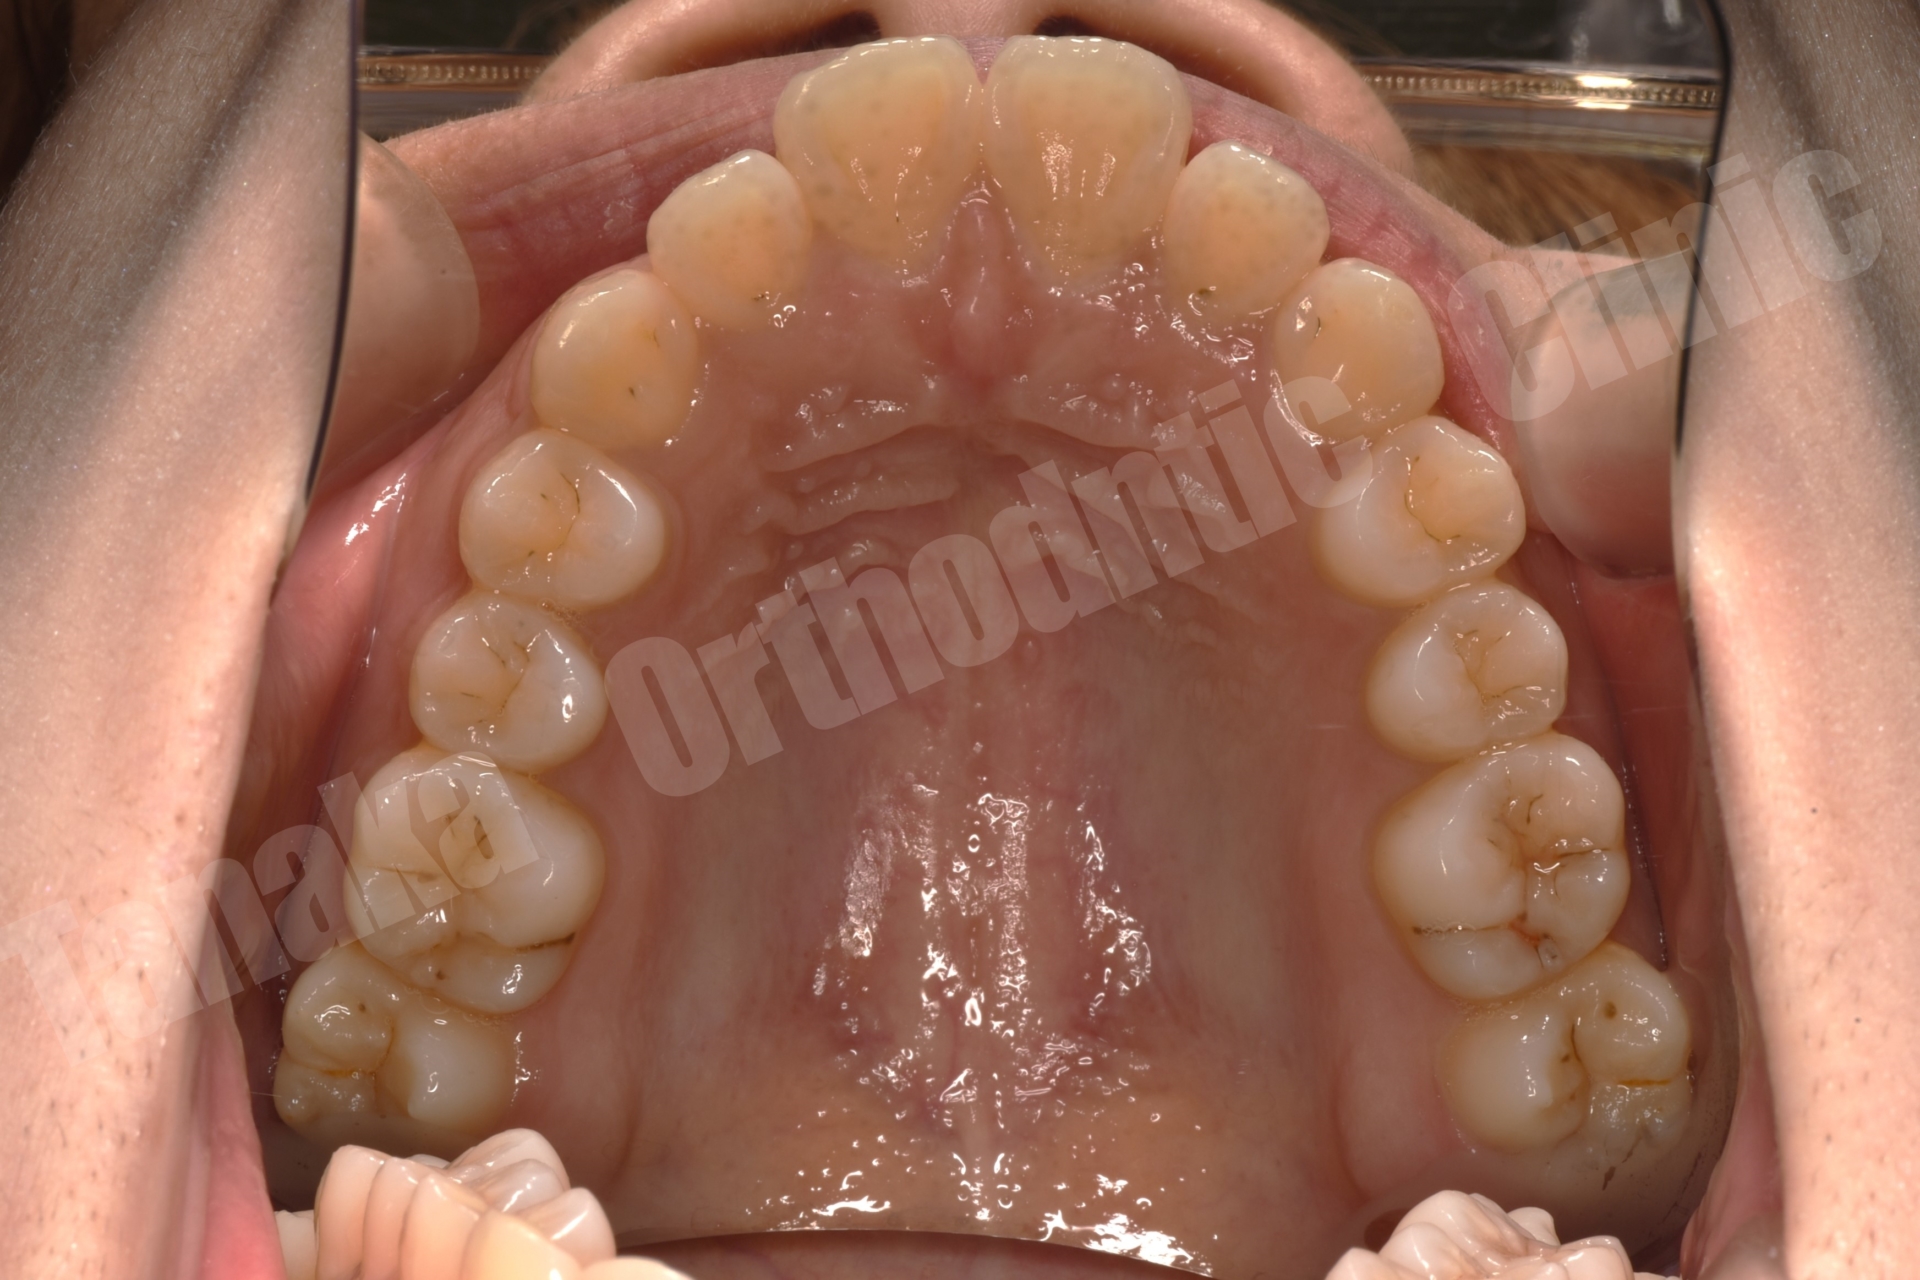

初診時の診査では、上顎前歯が唇側に傾斜しており、前歯の水平被蓋(オーバージェット)が大きい状態でした。そのため口元の突出感が認められ、前歯部は十分に噛んでいない状態でした。また下顎正中は左側へ偏位しており、右下E(乳臼歯)の残存と5番の先天欠如、さらに下顎両側7番の位置異常も確認されました。さらに患者様は10代半ばの頃に一度、非抜歯でマルチブラケット矯正を受けており、その影響もあって上顎中切歯には歯根吸収が生じ、歯根がやや短くなっている所見も認められました。

そこで治療では上下歯列に唇側マルチブラケット装置を装着し、歯列全体の排列を行いました。上顎前突を改善するため上顎両側4番を抜歯し、前歯を後退させて口元のバランスを整える計画としました。さらに下顎正中の改善のため右下Eを抜歯し、約11mmある乳臼歯部のスペース閉鎖を行う計画としました。このスペース閉鎖には矯正用アンカースクリューを使用し、右側6番・7番を近心移動させる必要があります。また治療途中で萌出してくる右下7番の位置を適切にコントロールすることも重要なポイントとなります。

今回の症例では、11mmという比較的大きなスペース閉鎖に加え、治療途中で萌出してくる7番のコントロールも必要となるため、通常より難易度の高い治療となりました。そのため治療期間は通常よりやや長くなる可能性を考慮し、2年以内での治療終了を目標として治療を開始しました。